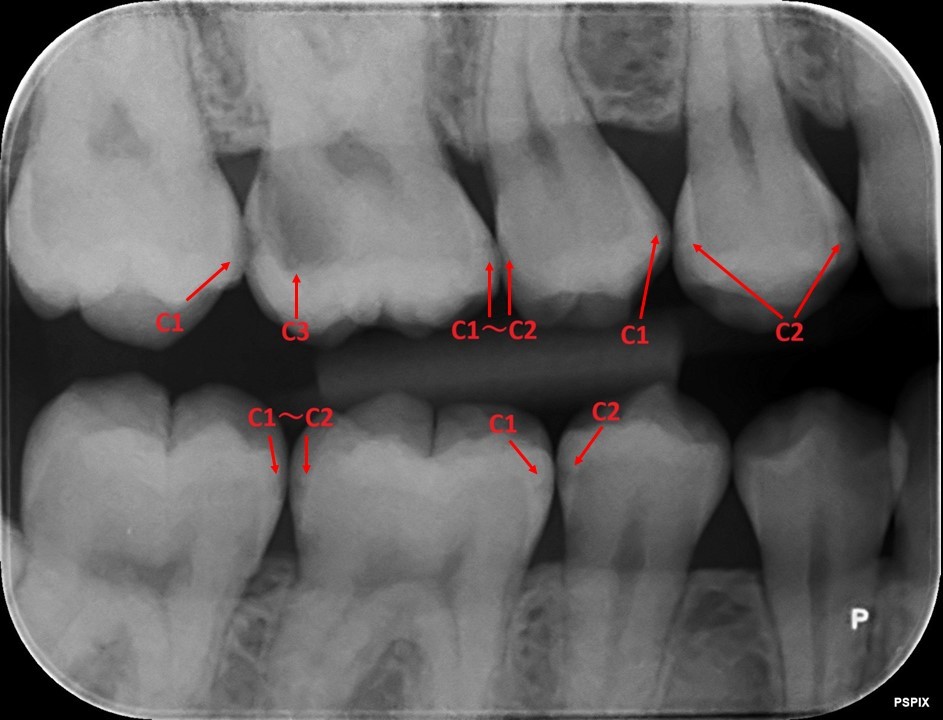

どこが虫歯かわかりますでしょうか?

この虫歯は大きいので分かりやすいです。

そうです。赤い丸の場所が虫歯です。隣の健康な歯と色を比べると全く違います。

この虫歯は「C3」です。神経まで達している虫歯なのでレントゲンでも分かりやすいと思います。

奥歯の虫歯なのですが、どこにあるかわかりますか?

正解は・・・

こちらが全て虫歯です。

よく見れば大きい「C3」の虫歯もありますが、小さい虫歯だらけの状態です。

虫歯は歯と歯の間から虫歯になっているために、患者さん自身では気づいていませんでした。

ここで「C1~C2」とあります。虫歯はが大きくなると判別つきやすいのですが、小さいものは正確に範囲が分からないことが多いです。

ですのでレントゲンからでは、虫歯があるのは分かりますが「C2まで進行しているかなぁ?」と推測することまでしか出来ません。

実際に治療をすると「C2」だったと後で分かります。